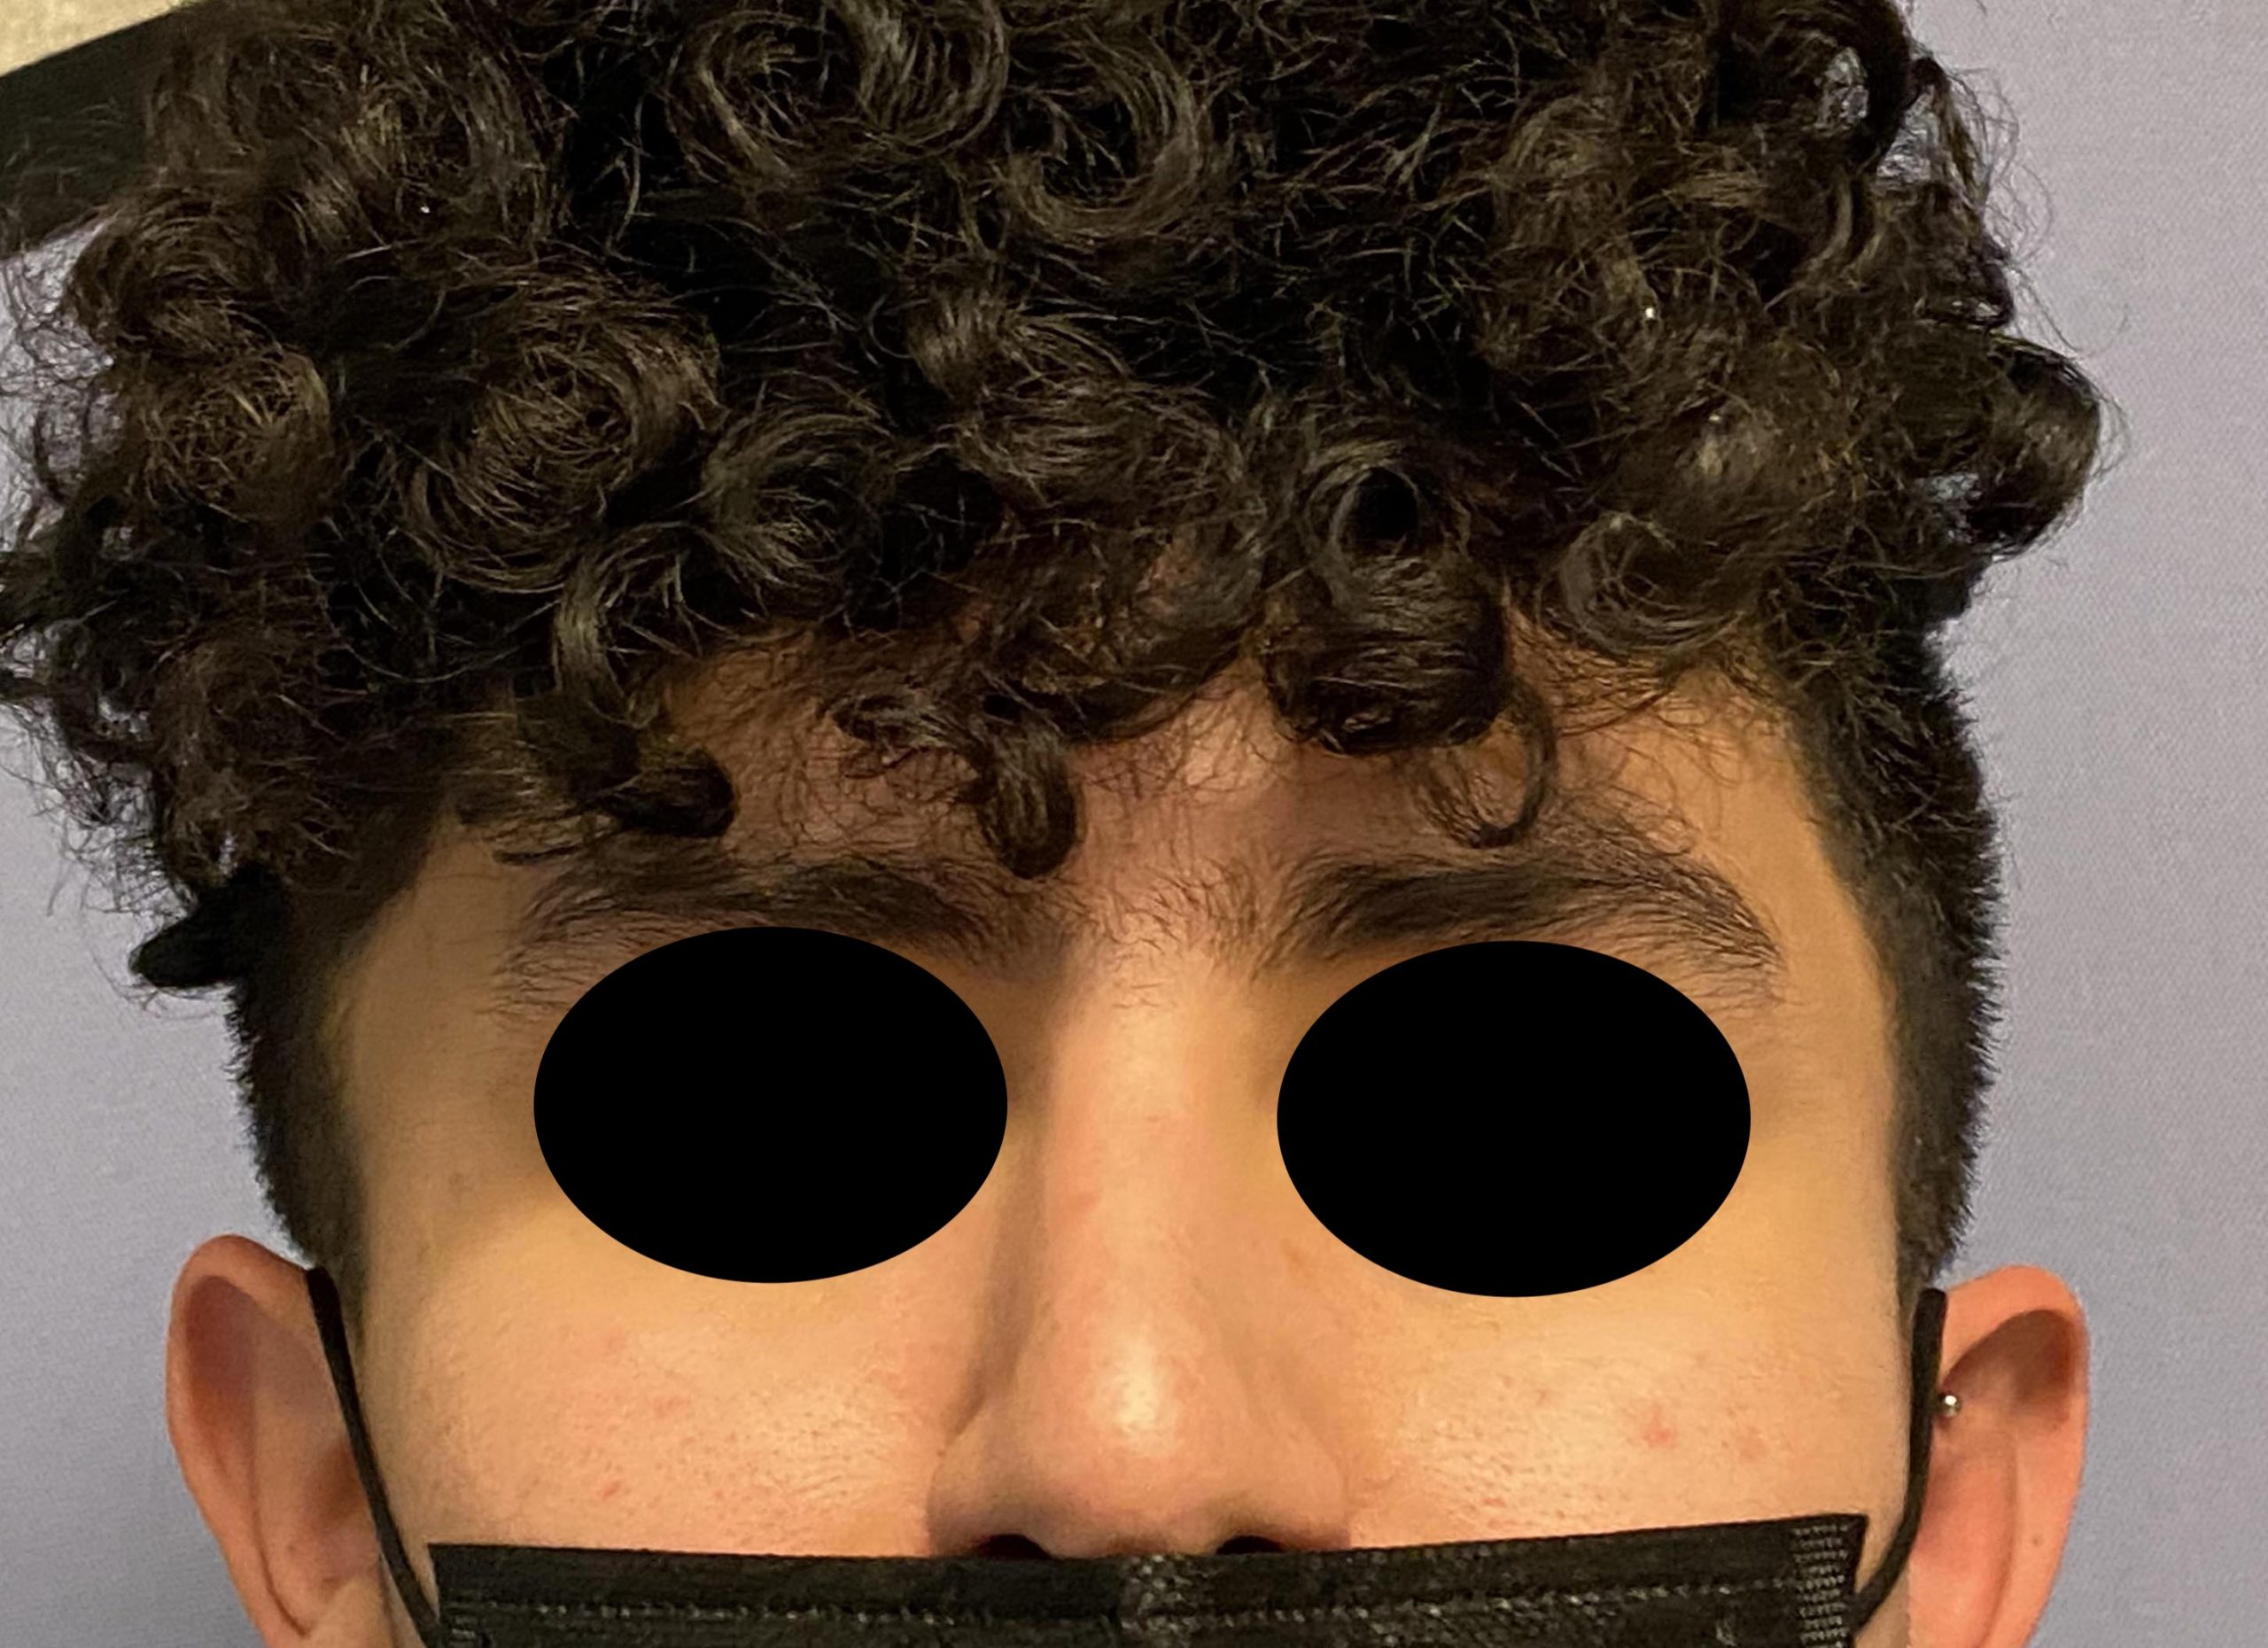

Patient 82

Young male seeking reduction of his convex sides of his head.

Head width reduction by posterior temporal muscle reduction through hidden postauricular incisions behind the ears.

Young male seeking reduction of his convex sides of his head.

Head width reduction by posterior temporal muscle reduction through hidden postauricular incisions behind the ears.